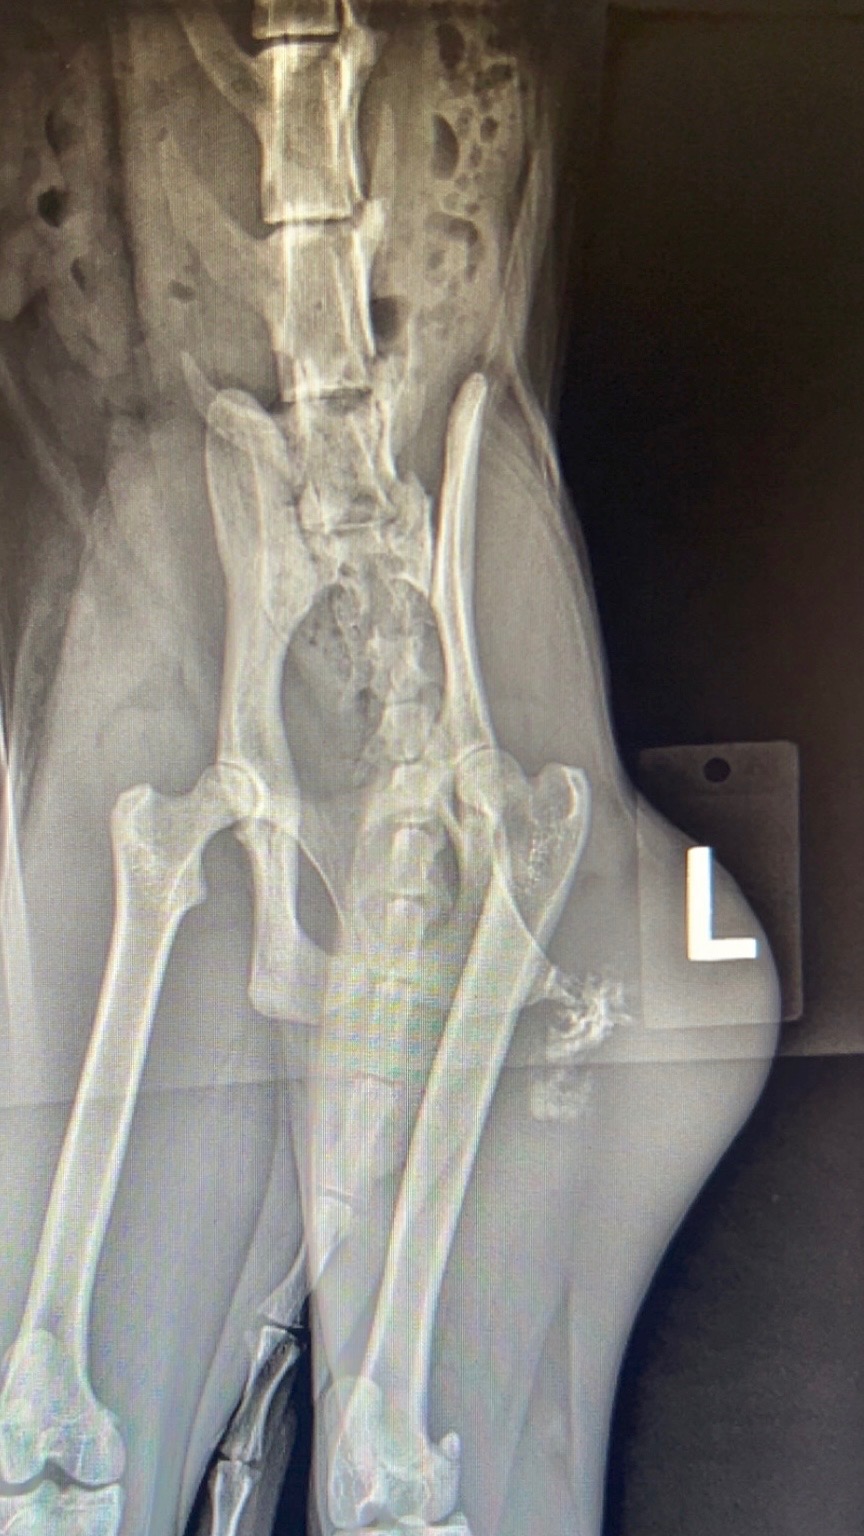

It pains me to ask for help like this but my fiancé and I are left with broken hearts and no other options. 2 weeks ago we found an aggressive fibrosarcoma on our baby Looney’s back leg at only 1 year old. It grew big and fast in less than a month from when she last had her annual vet visit at my work. We immediately scheduled for surgery with oncology specialists to amputate, praying we weren’t too late, and that it hadn’t spread. The CT scans revealed no signs of metastasis into major organs, leaving her team confident they could remove most of it by amputation, but that she would still need radiation therapy afterward to prevent regrowth. I’m only a vet assistant working through vet nursing school and the discounts we receive for working in the field barely make a difference. We’ve maxed out our care credit card and other credit cards to afford just the CT scan, amputation surgery, and biopsy, only to find out that the radiation treatment will cost another $12,000. We can’t imagine loosing our little girl and seeing the depression her mom, dad, and sisters would go through without her. They are all so bonded being littermates with their parents. We’ve had her since the day she was born and love her more than words can say. 1 year isn’t enough time with her. Please help us save our baby. If you can’t contribute, even a share, or a simple prayer for her means the world to us. Thank you for even taking the time to hear our story❤️